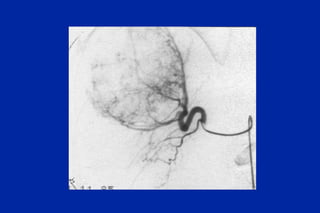

Este documento resume los principales tipos y técnicas de angiografía. Describe brevemente la angiografía, arteriografía, flebografía y linfografía, así como las técnicas de contraste y materiales utilizados. También explica los principales accesos vasculares, la técnica de Seldinger, la angiografía por sustracción digital y algunas técnicas endovasculares comunes.